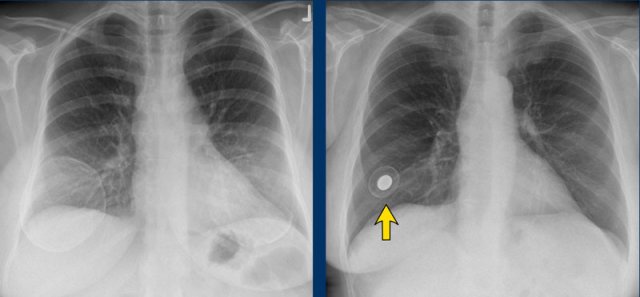

X-Ray and CT

Chest X-Rays and CT do not play a role in examining breast implants.

Sometimes they can be detected on X-rays for instance when there are capsular calcifications or when a filling valve of an expandable prosthesis is seen (arrow).

Also on CT sometimes complications can be seen, but usually CT does not give adequate information about the integrity of the prosthesis.

The chest film shows capsular calcifications in a medially displaced breast implant, which is not parallel to the breast contour.

The CT of the same patient shows also calcifications at the posterior side not following the contour of the implant indicating intracapsular rupture (arrow).